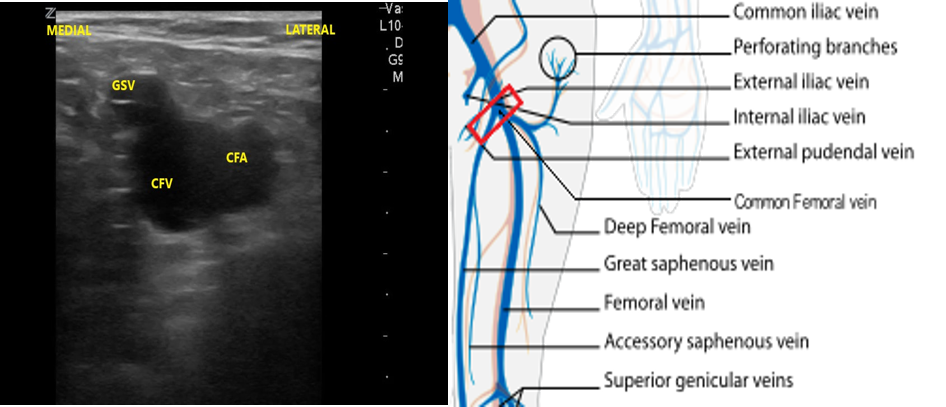

- Slide the transducer distally 1 to 2 cm to the junction of the CFV and GSV ( 10 and 11) and compress.

- Figure 10. Junction of the CFV and GSV 1-2 cm below the inguinal canal with transducer orientation indicated (red rectangle).

- Figure 11. Compression of the CFV at the junction of the GSV 1-2 cm below the inguinal crease.